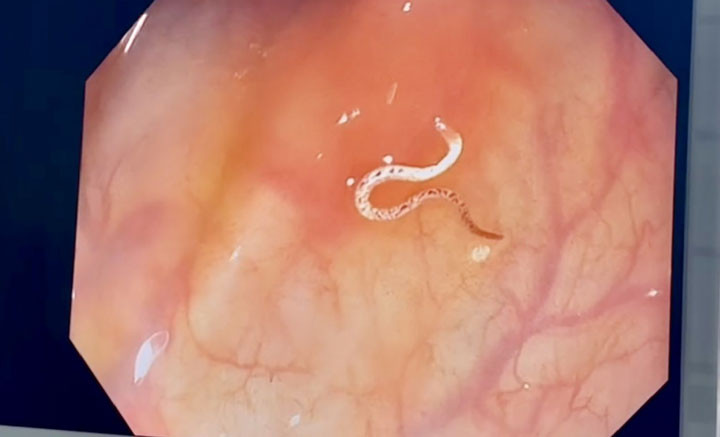

Trong quá trình nội soi đại tràng gây mê cho người bệnh, bác sĩ đã phát hiện kí sinh trùng (nghĩ nhiều đến giun móc), 1 đầu cắm sâu vào lòng đại tràng. Các bác sĩ đã nhanh chóng gắp kí sinh trùng và gửi xét nghiệm cho kết quả giun móc.

| Hình ảnh con giun trong đại tràng của người bệnh |